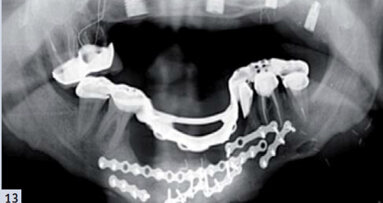

Les procédures décrites ci-dessus peuvent également être réalisées dans les cas prévoyant une prothèse conjointe (fixe) pour la réhabilitation de l’arcade entière (Figs. 11a et b, Figs. 12a–c), ainsi que dans les cas où certaines dents naturelles sont parodontalement stables et peuvent servir de piliers prothétiques. Dans ces cas, la prothèse complète peut être immédiatement conçue comme prothèse de recouvrement. Une réplique prothétique pourrait être fabriquée sur la base de cette prothèse de recouvrement, et de nouveau utilisée comme décrit précédemment (Figs. 13 a-c).

La porcelaine est un matériau envisageable pour la céramisation des armatures de prothèse conjointe. Si l’angulation des implants ne permet pas la prise d’empreintes selon la technique décrite plus haut et si une prise d’empreinte à ciel ouvert est préférable, les fenestrations peuvent être pratiquées dans la réplique prothétique (Fig. 14).